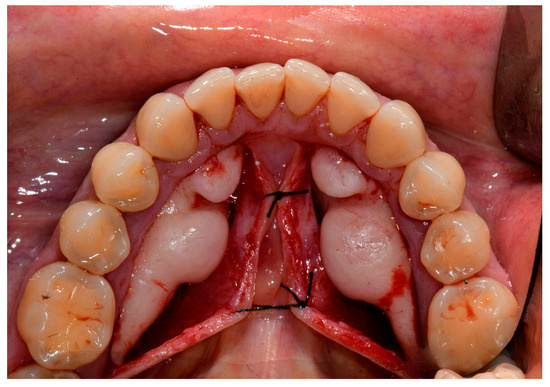

3. Treatment